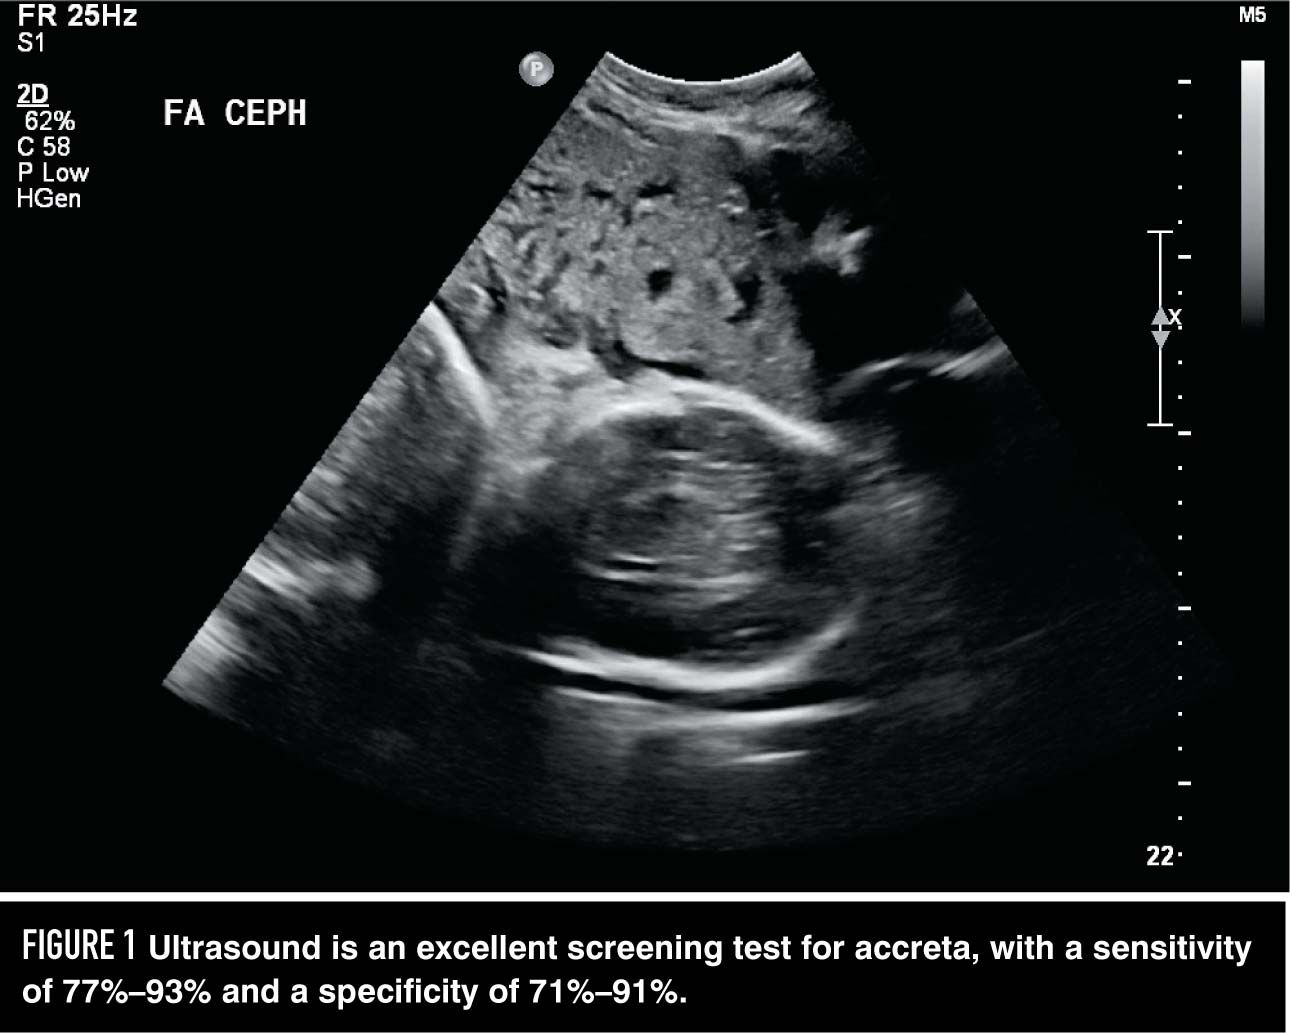

Discover the placenta is posterior meaning and what it signifies for your pregnancy. Learn how a back-of-the-uterus placement affects fetal movement, labor, and your ultrasound experience. Get expert insights into this common placental position and understand why having a posterior placenta is typically considered a normal, healthy finding for expecting mothers.